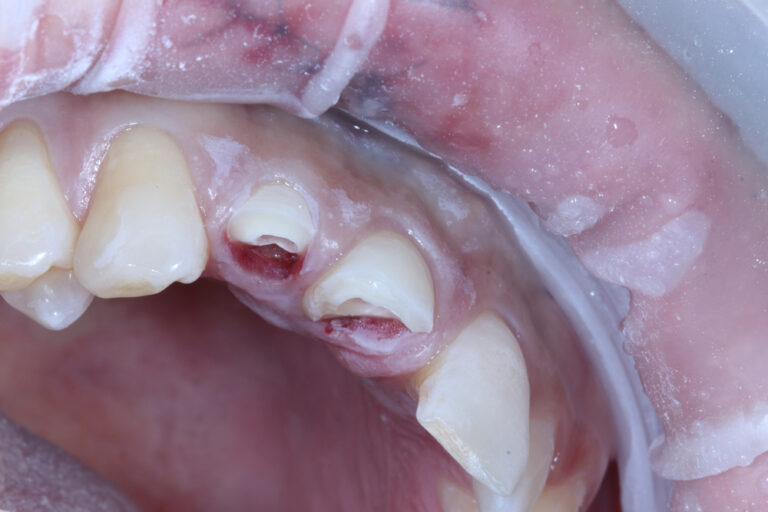

• 앞니 2개가 깨진 상태(치아 파절)

• 잇몸/입술 부위에 타박·열상(찢어짐)

• 파절면이 커서 심미적으로도 바로 불편한 상황

덜렁거리는 치아조직을 제거하고 나니 치아 파절선이 생각보다 깊어서 뽑아야 하나? 생각했지만 동생이라 나중에 필요하면 그때 뽑자는 마음으로 치아에 기둥을 세워서 크라운을 하는 방식을 선택했어요.